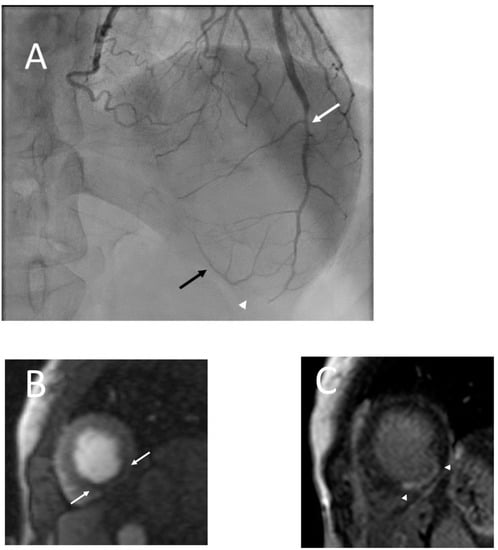

Figure 5.

Series shows catheter angiogram (A) which shows moderate stenosis of the mid left anterior descending coronary artery (LAD; white arrow) and occlusion of the distal LAD (white arrowhead) with distal collaterals (black arrow). No other significant stenosis in rest of the coronary arteries (not shown) seen, findings which are consistent with SCAD. Cardiac MR (B,C) performed later revealed resting perfusion defect (B) in the apical inferior wall (arrow) with corresponding subendocardial (near 75%) late gadolinium enhancement (arrowhead; C) consistent with an infarct in the distribution of the left anterior descending coronary artery. Three days after discharge and cardiac MR, the patient presented again with band-like c lower chest pain and coronary CT angiogram (D,E) was performed. Curved planar reformat (D) and volume rendered (E) images now revealed focal severe stenosis (white arrows) in the mid LAD with recanalization of the distal segment (arrowhead) compared to the catheter angiogram performed five days prior.